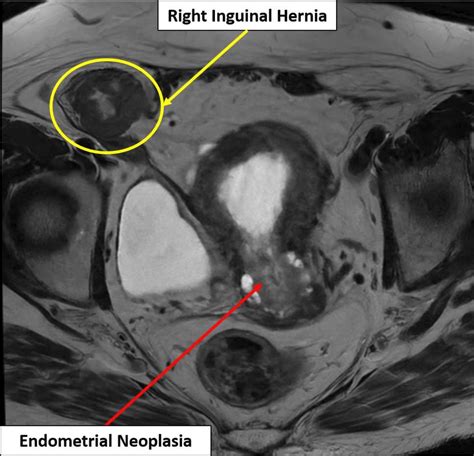

Diagnosis of an Incarcerated Inguinal Hernia

Diagnosing an incarcerated inguinal hernia typically involves a combination of a physical examination and imaging tests. The healthcare provider will:

• Examine the groin area for a visible bulge and tenderness.

• Ask about symptoms such as pain, nausea, and difficulty passing gas.

• Order imaging tests such as an ultrasound or CT scan to confirm the diagnosis and assess the extent of the incarceration.

Imaging tests are crucial for determining the severity of the incarceration and whether there is any sign of strangulation. An ultrasound can provide a clear view of the hernia and the surrounding tissues, while a CT scan can offer a more detailed image of the abdominal area.